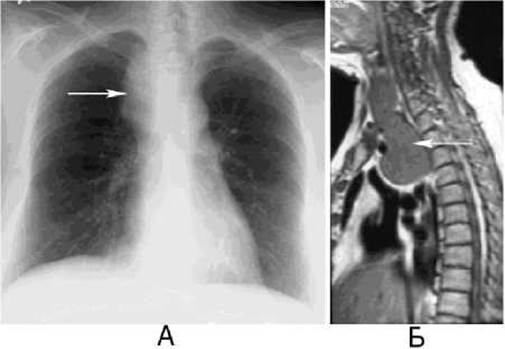

Мал. 131. Невринома (стрілка) та типова локалізація захворювань органів середостіння (рентгенографія).

А - пряма проекція; Б - бічна проекція.

Локалізація патологічного утвору у середостінні на рентгенограмі у прямій проекції характеризується наявністю патологічної тіні з переважаючим вертикальним розміром, що формує зверху та знизу з серединною тінню тупі кути (мал. 131 А). Об’ємний утвір відхиляє середостінну плевру назовні, майже нерухомий під час Дихання.

Визначення локалізації патологічної тіні на рентгенограмі органів грудної клітки у бічній проекції, або на КТ чи МРТ, часто є вирішальним фактором для виявлення природи захворювання і постановки діагнозу (мал. 131Б).

Невриноми (неврилемоми) - доброякісні пухлини, що розвиваються з нервової тканини, частіше із спинномозкових вузлів. Розміщуються невриноми біля хребта, ростуть повільно, безсимптомно, можуть досягати великих розмірів, тоді з’являється тупий ниючий біль у спині, грудях, що ірадіює за ходом міжребрових нервів. Рентгенологічно виявляється інтенсивна однорідна тінь округлої або овальної форми з чіткими рівними контурами, яка зливається з тінню середостіння і хребтового стовпа, не зміщується при диханні. При значних розмірах невриноми часто спостерігаються розширення міжхребцевого отвору, крайові дефекти задніх відділів ребер, бічних поверхонь і поперечних відростків тіл хребців.